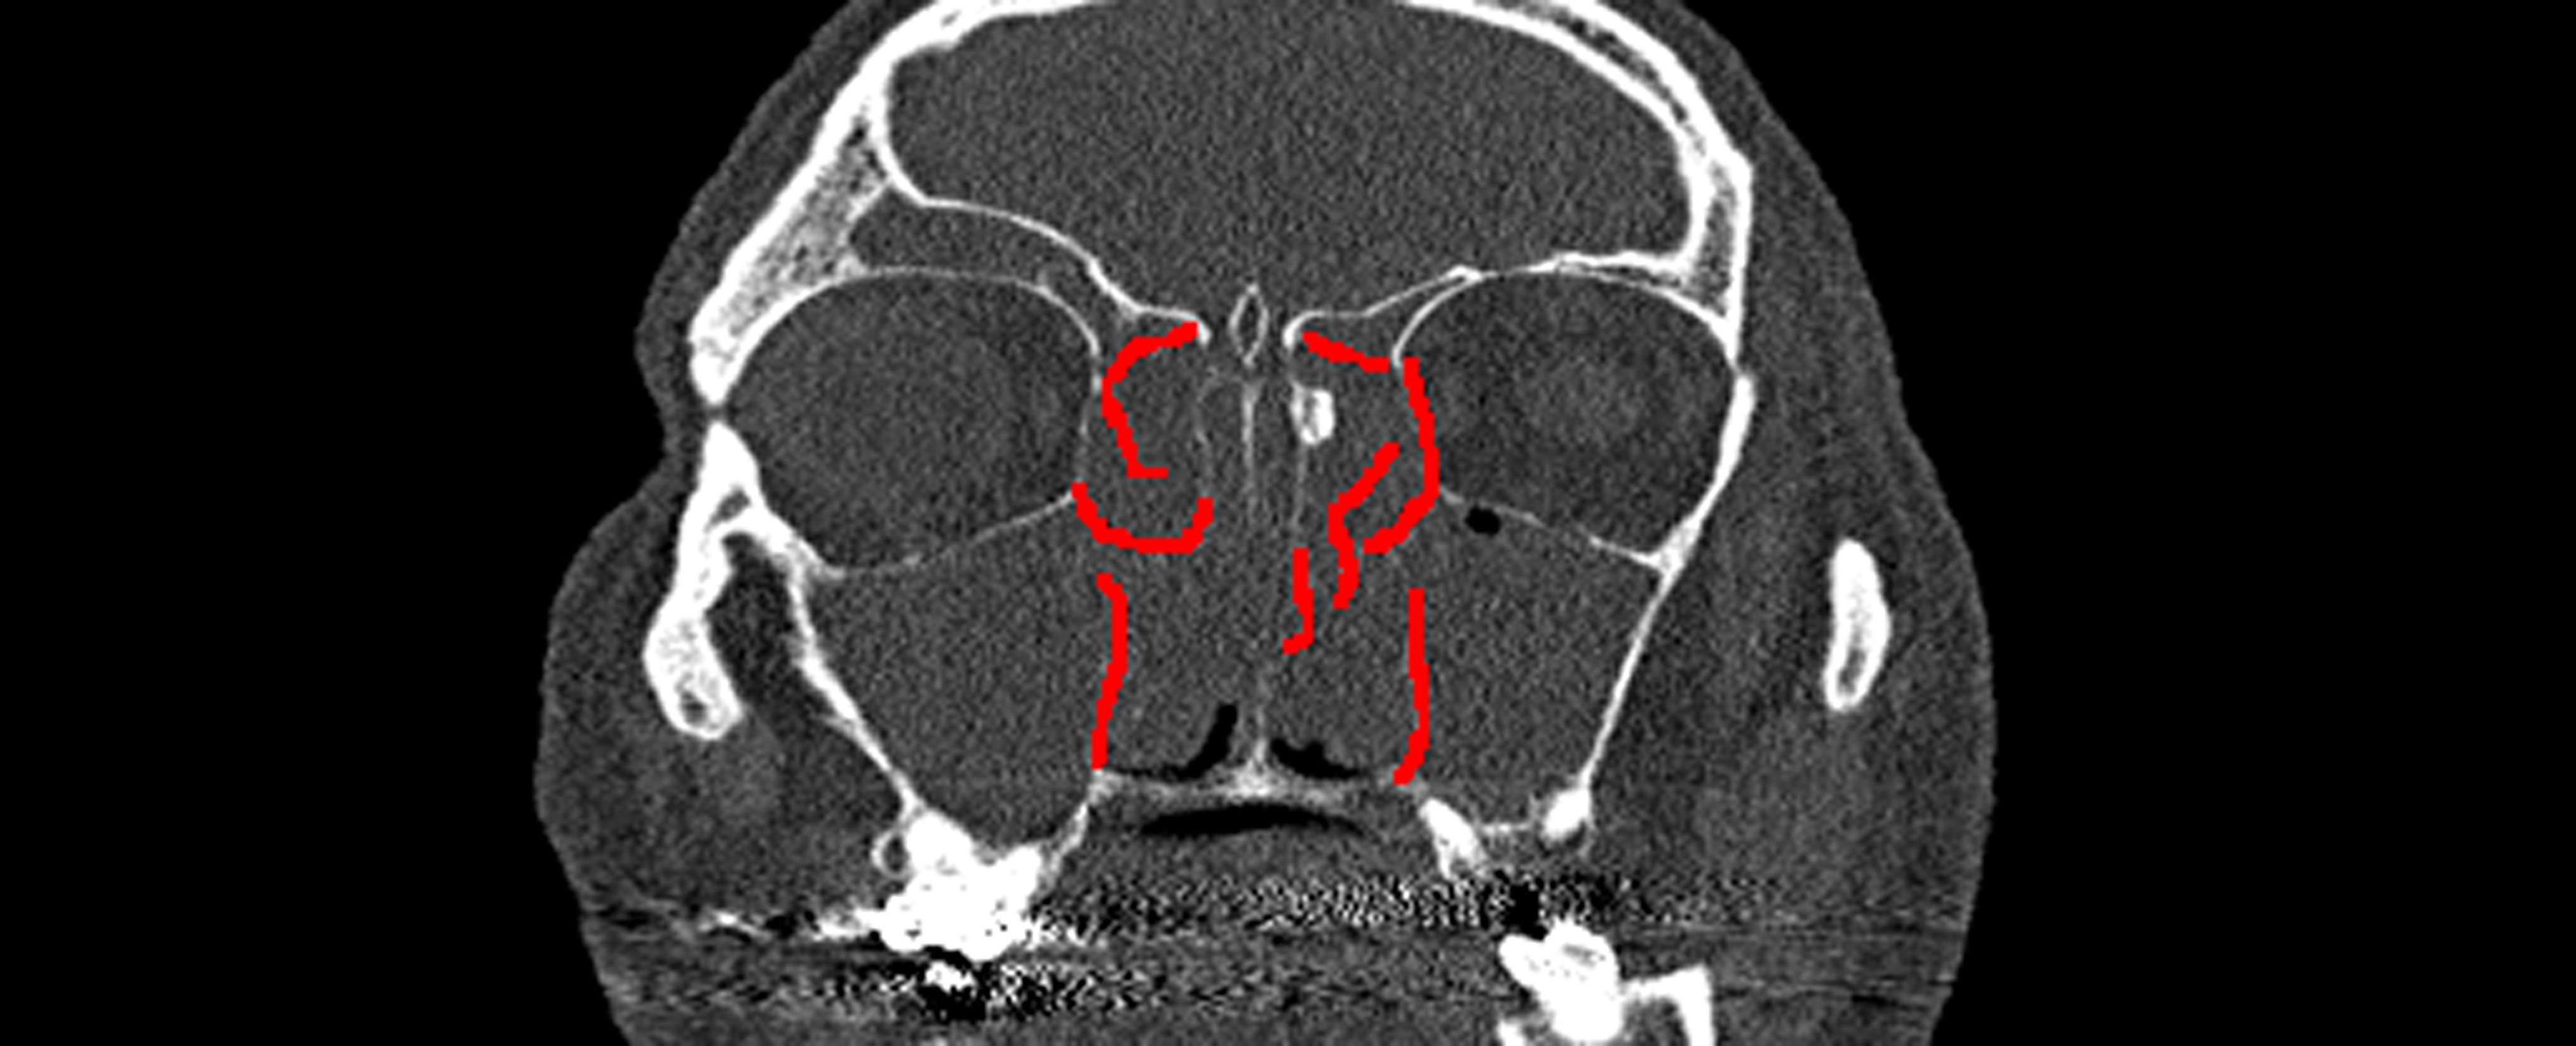

Cerebral Insight

HemoDetect: An AI based Assistant for Diagnosis of Brain Hemorrhage.